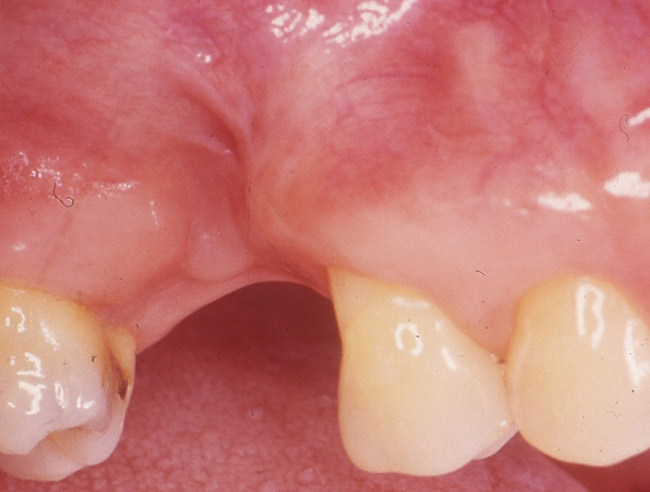

Figure 1b  Occlusal view of the alveolar ridge after extraction of tooth No. 3. This site will require ridge augmentation before placement of a dental implant–supported restoration.

Figure 1c  Buccal view of the alveolar ridge after extraction of tooth No. 3.

Figure 1c